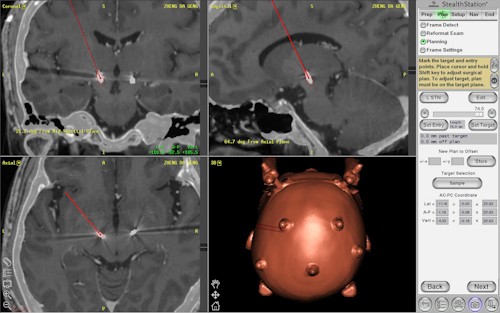

圖:固定好頭架後,鄭大耿再進行電腦斷層掃瞄(CT),精算手術靶點與模擬手術路徑。

右圖:電腦斷層掃瞄後,結合3T高磁場核磁共振檢查與定位導航技術,陳新源主任(左一)、洪祥益醫師(左二)與李毅醫務秘書(右二)立即討論模擬手術路徑。

左圖:陳新源主任以導航系統定位手術座標。

十日上午八點,在進行深層腦部刺激術之前,由神經外科陳新源醫師為鄭大耿裝上立體定位頭架;固定好頭架後,再進行電腦斷層掃瞄(CT),結合3T高磁場核磁共振檢查與定位導航技術,為鄭大耿精算手術靶點與模擬手術路徑,獲得需刺激的正確定位。「未來加油,感恩慈濟」在手術室前,鄭大耿感受到花蓮慈院醫療團隊的努力,讓他很安心,儘管表達困難,他還是奮力地說出心中的感恩。害羞面對鏡頭的爸爸鄭廣湯,也是帶著燦爛的笑容,全程雙手合十感恩醫療團隊的用心。

圖說:手術後,鄭大耿的兩側視丘下核晶片植入的磁振造影與電腦斷層融合影像定位圖。